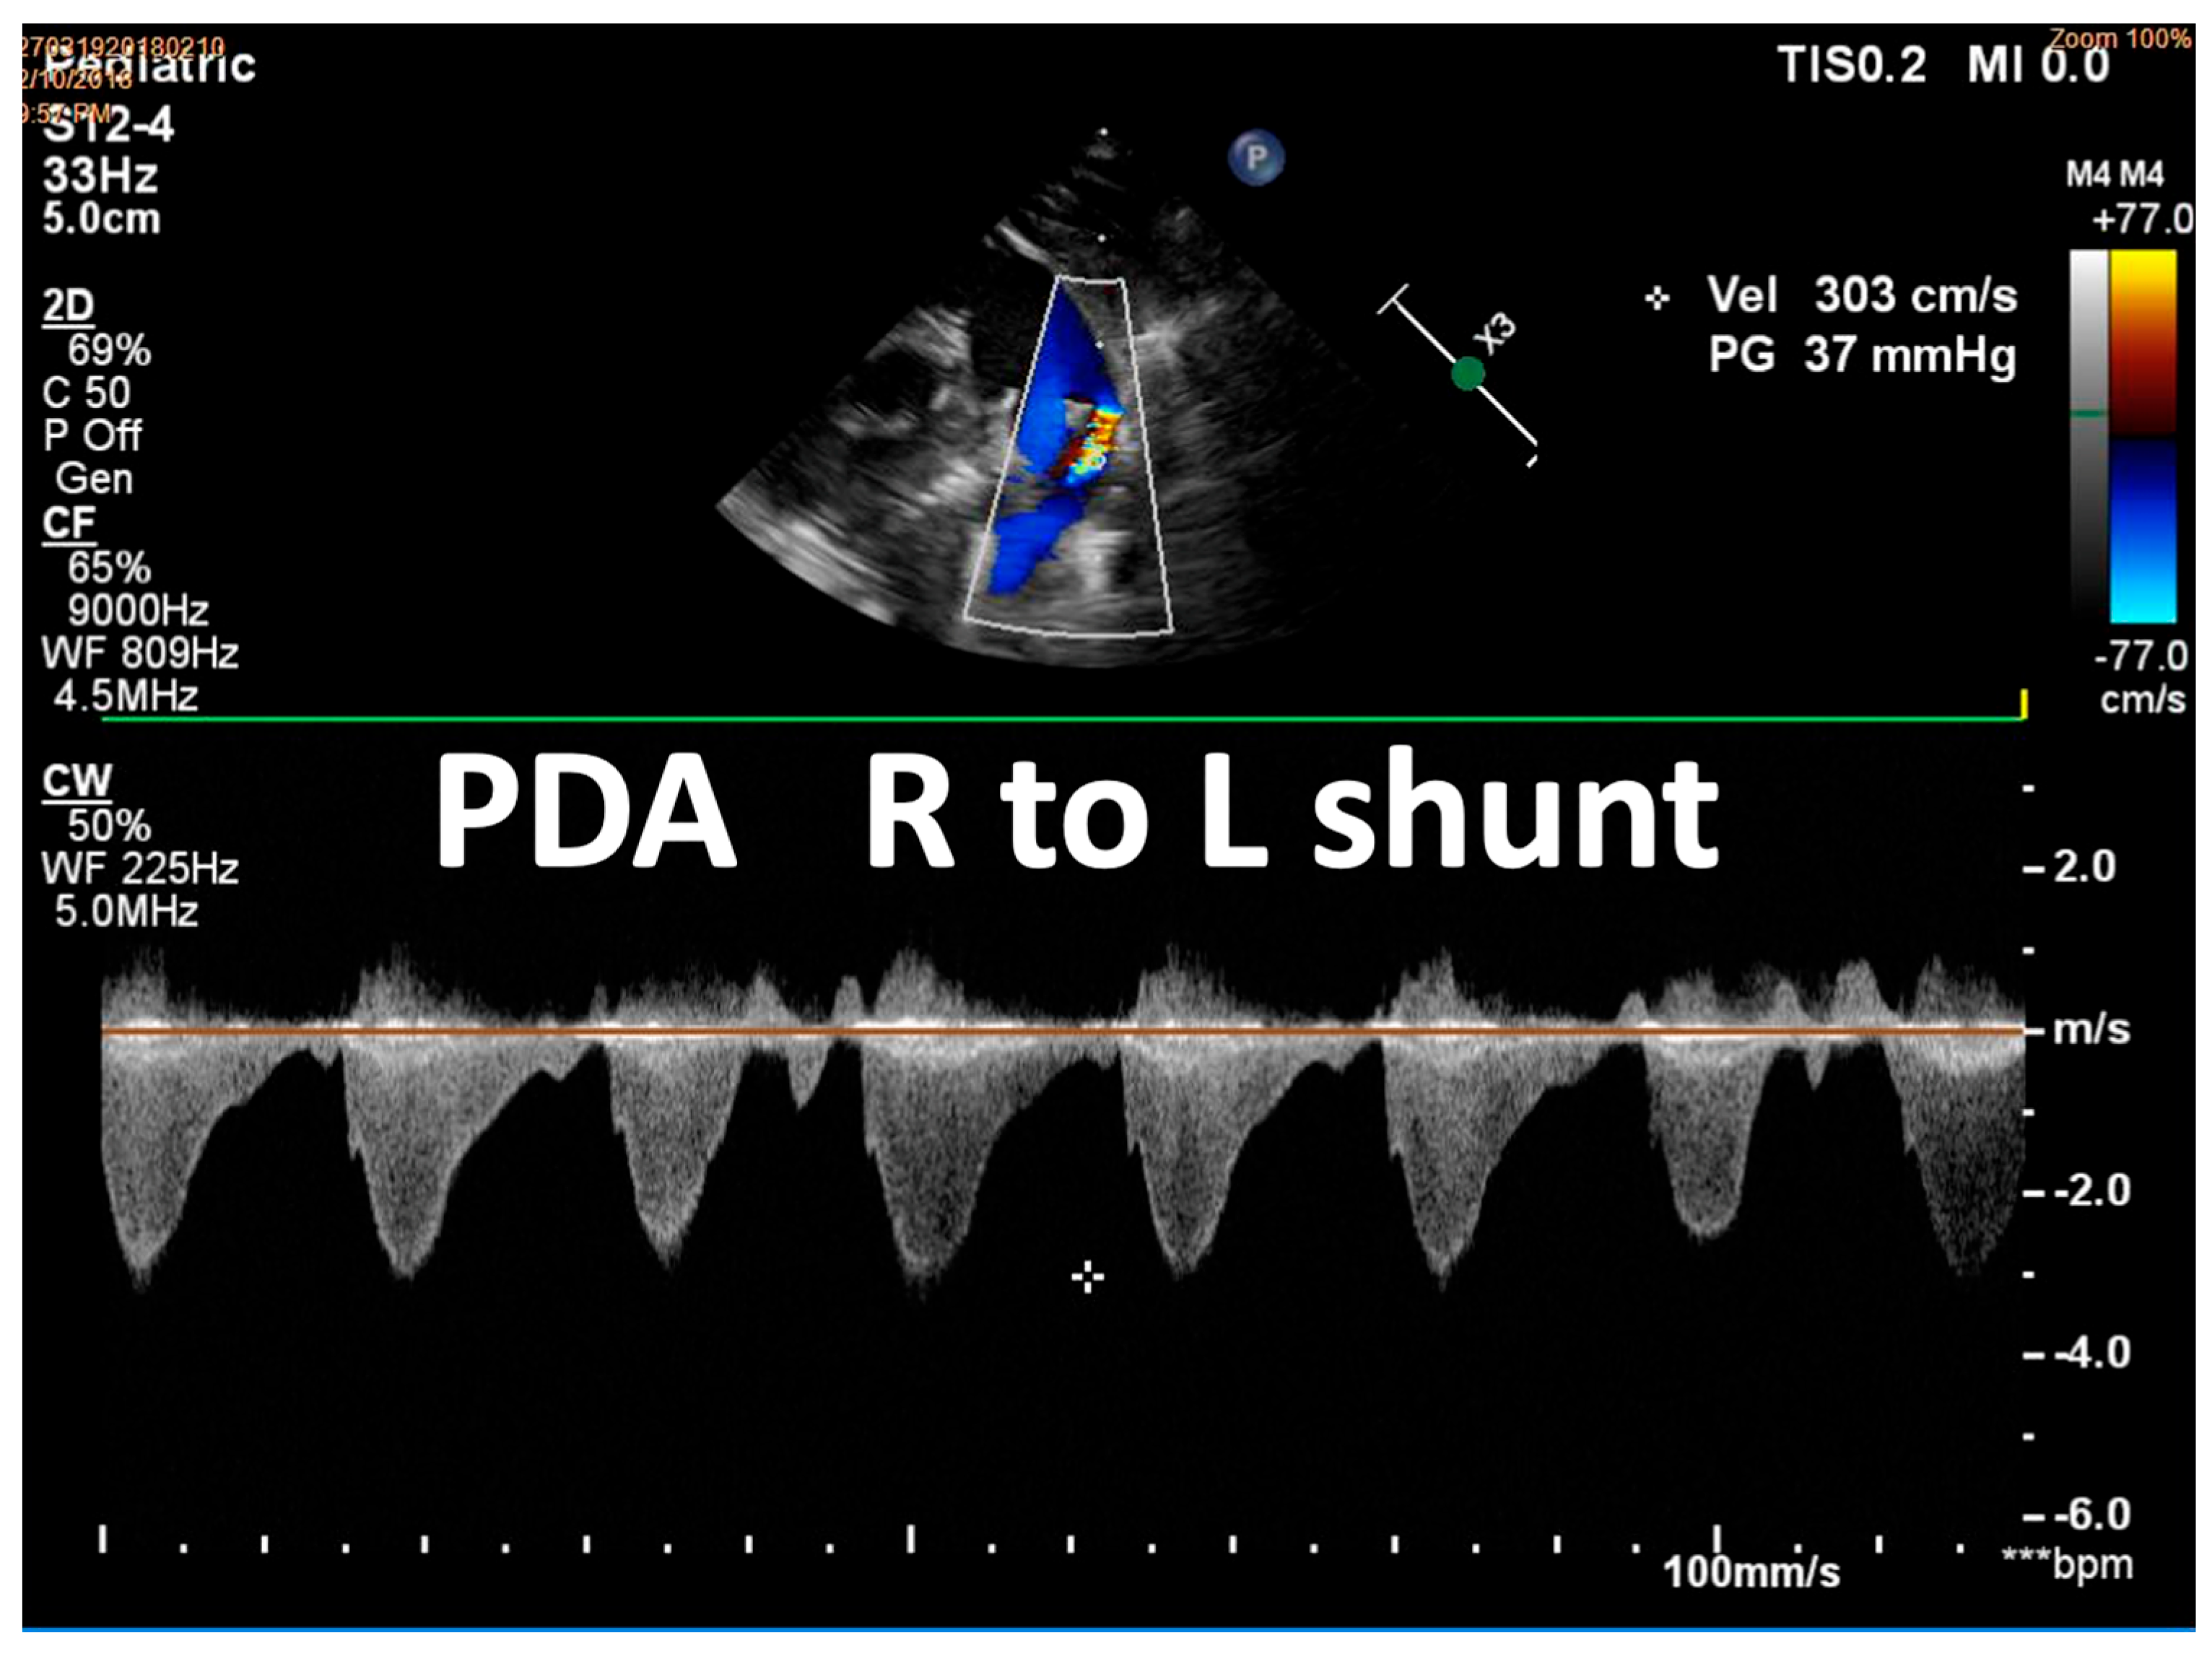

| Detection of Shunt | Identification and assessment of flow through the patent foramen ovale (PFO) and ductus arteriosus (PDA) | Indicates the presence and nature of pathological flow: left-to-right, bidirectional (often in moderate PPHN), or right-to-left (in very severe PPHN) |